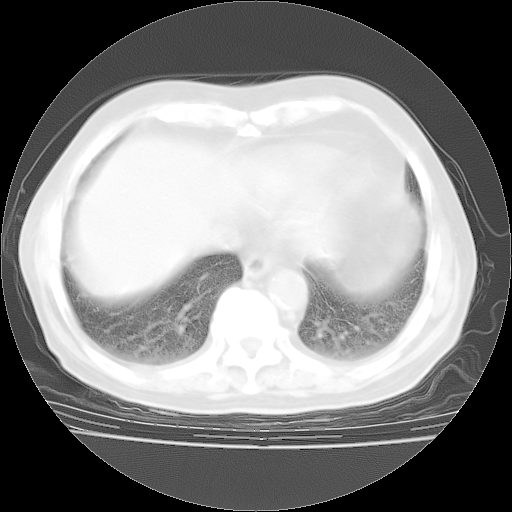

4月28日肺部CT——再次出现类似去年5月9日——透光度降低,“间质性”改变。

4月28日肺部CT——再次出现类似去年5月9日——磨玻璃样、间有“粟粒样”改变。

个人阅读4.14日肺部CT平扫:纵隔窗无异常,但肺窗示:双下肺内、后基底段有片絮状侵润影,部位以后基底段为著,以间质改变为主,呈急性肺泡炎征像,和首次住院影像学有相似之处。仅是个人读片,明日请相关专家再读片哈。其它建议同上。